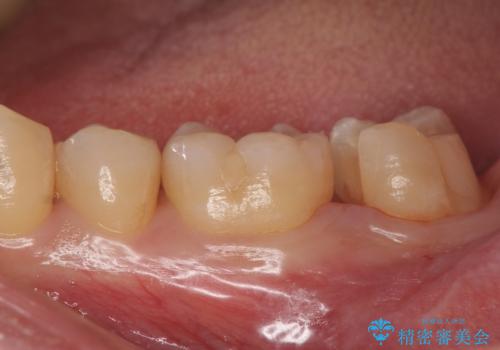

二つの提案をしたところ、①を選択されたのでゴールドインレーによる治療を行いました。

ゴールドインレーは歯質との適合がよく

虫歯の再発リスクや割れるというリスクが低いです。

しかしご自身での口腔内ケアを怠っていると虫歯の再発リスクは高くなるので

定期的にメンテナンスにくることをお勧めします。